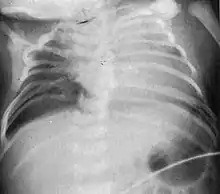

Radiograph depicting typical skeletal features of Jarcho-Levin syndrome, subtype spondylothoracic dysplasia. Note fanlike configuration of the ribs, with extensive posterior fusion, along with multiple vertebral segmentation defects. | |

Spondylothoracic dysplasia, or STD, has been repeatedly described as an autosomal recessively inherited condition that results in a characteristic fan-like configuration of the ribs with minimal intrinsic rib anomalies. Infants born with this condition typically died early in life due to recurrent respiratory infections and pneumonia due to their restricted thorax.[3][4][5] Recently, a report[6] has documented that actual mortality associated with STD is only about 50%, with many survivors leading healthy, independent lives.